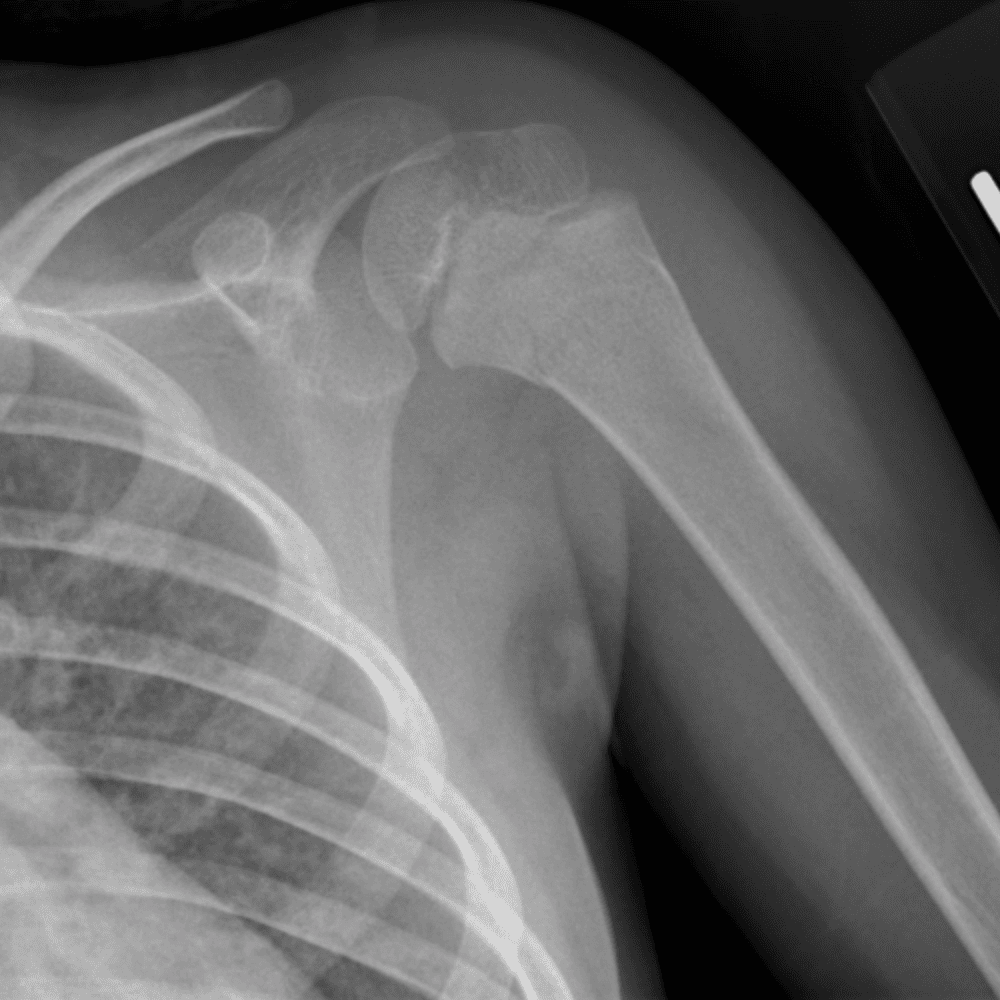

Simuliert den Dienst durch subtile oder schwierige Fälle und einige Normalbefunde.

30 Fälle